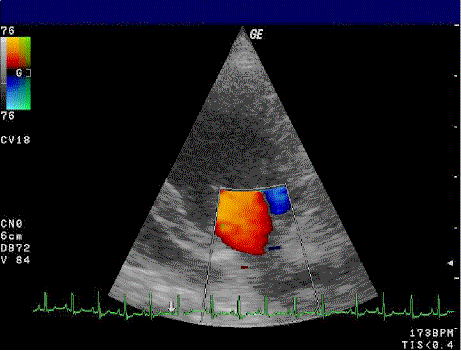

What does BART stand for?

blue away from probe, red towards probe